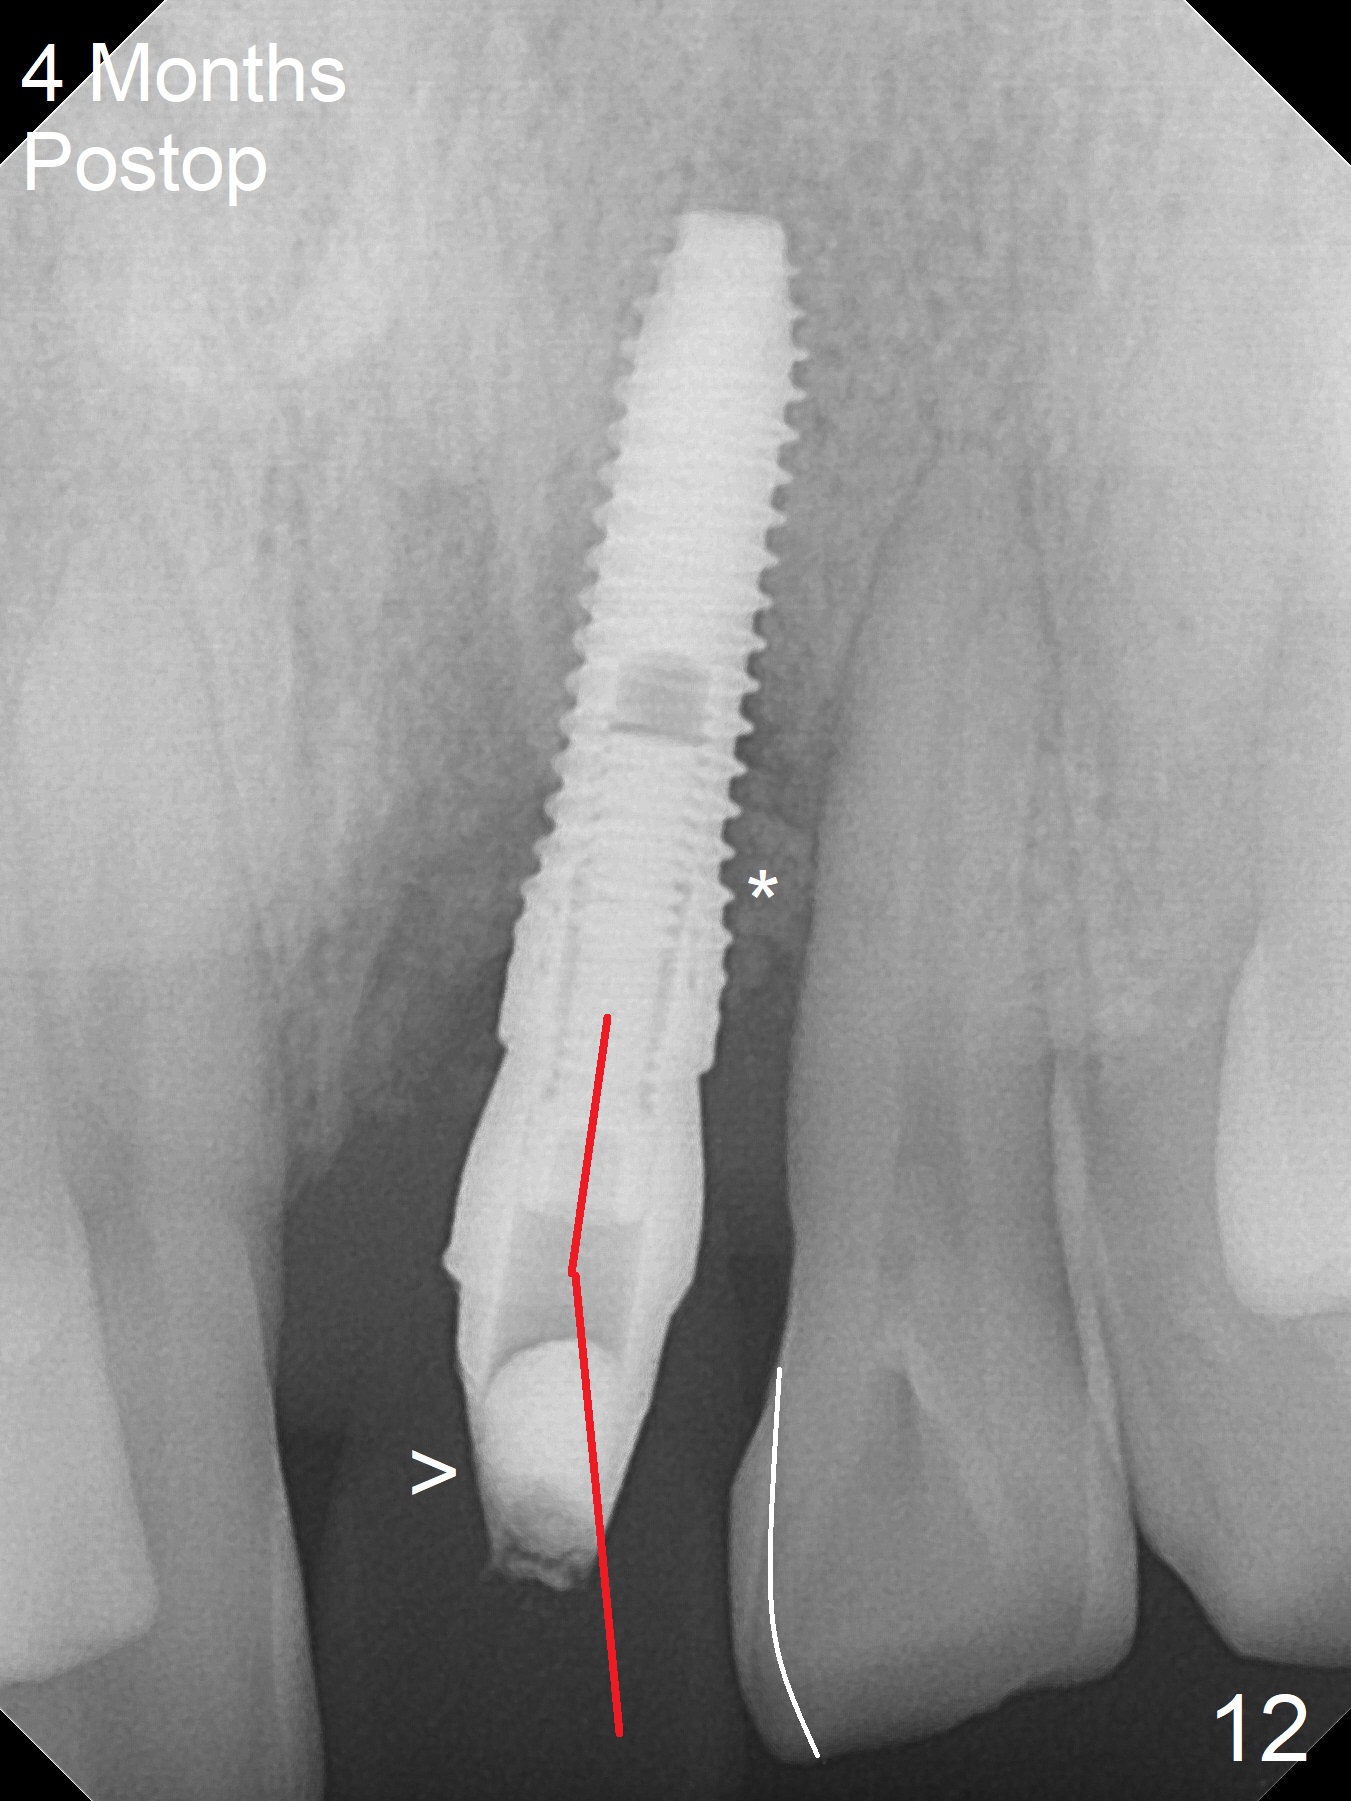

Immediately preop PA confirms loss of the buccal plate at #9 (Fig.1 *). In contrast the palatal crest is ~ 4 mm subgingival (WNL) after extraction. When initial osteotomy reaches 18 mm, there is moderate hemorrhage, probably due to close to the nasal floor (Fig.2 red dashed line). Following sequential osteotomy, a 3.8x15 mm dummy implant is placed partially (Fig.3 (pink: apical osteotomy)). After placement of an implant with the same dimension as the dummy's (Fig.4), PRF is laid against the inner surface of the buccal defect and allograft (Fig.5 *) is packed mainly in the buccal gap before and after insertion of a 4.5x5(4) mm abutment. The patient is satisfied with the immediate provisional (Fig.6: 1 week postop). The buccal margin of the provisional is shortened with exposure of bone graft to facilitate gingival downgrowth (Fig.6: 1 month postop). The buccal plate seems to collapse nearly 2 months postop (Fig.8 *), probably due to loss of the bone graft. The abutment is exposed buccally (Fig.9). The margin of the abutment is reprep and the provisional is relined so that the margin of the provisional is palatal to the buccal gingival margin. In 2-3 weeks, a temporary abutment will be used to bulk the buccal gingiva. The gingiva seems to have downgrown; the buccal plate collapse appears normal nearly 3 months postop (Fig.10). The patient is more concerned about cross bite at #7. A temporary abutment is not used. The bone graft remains in place 3.5 and 4.5 months postop (Fig.11,12 *). Between 3 and 4 months postop, the mesial surface of the abutment has been trimmed (Fig.12 >). Since the mesial surface of the tooth #10 will be reduced (white curved line) to correct the upper dental midline, an angled abutment (red line) seems to be necessary to shift the provisional distal.